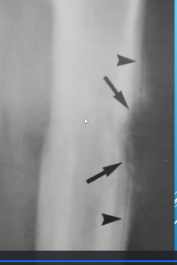

Kyste osseux simple :

- Humérus ++ , fémur prox

- 3-14 ans

- Lésion cystic (rempli de fluide)

- Lésion géographique

- Associé au « fallen fragment sign »

- Souvent ass à une fx patho

- N’est pas expansible